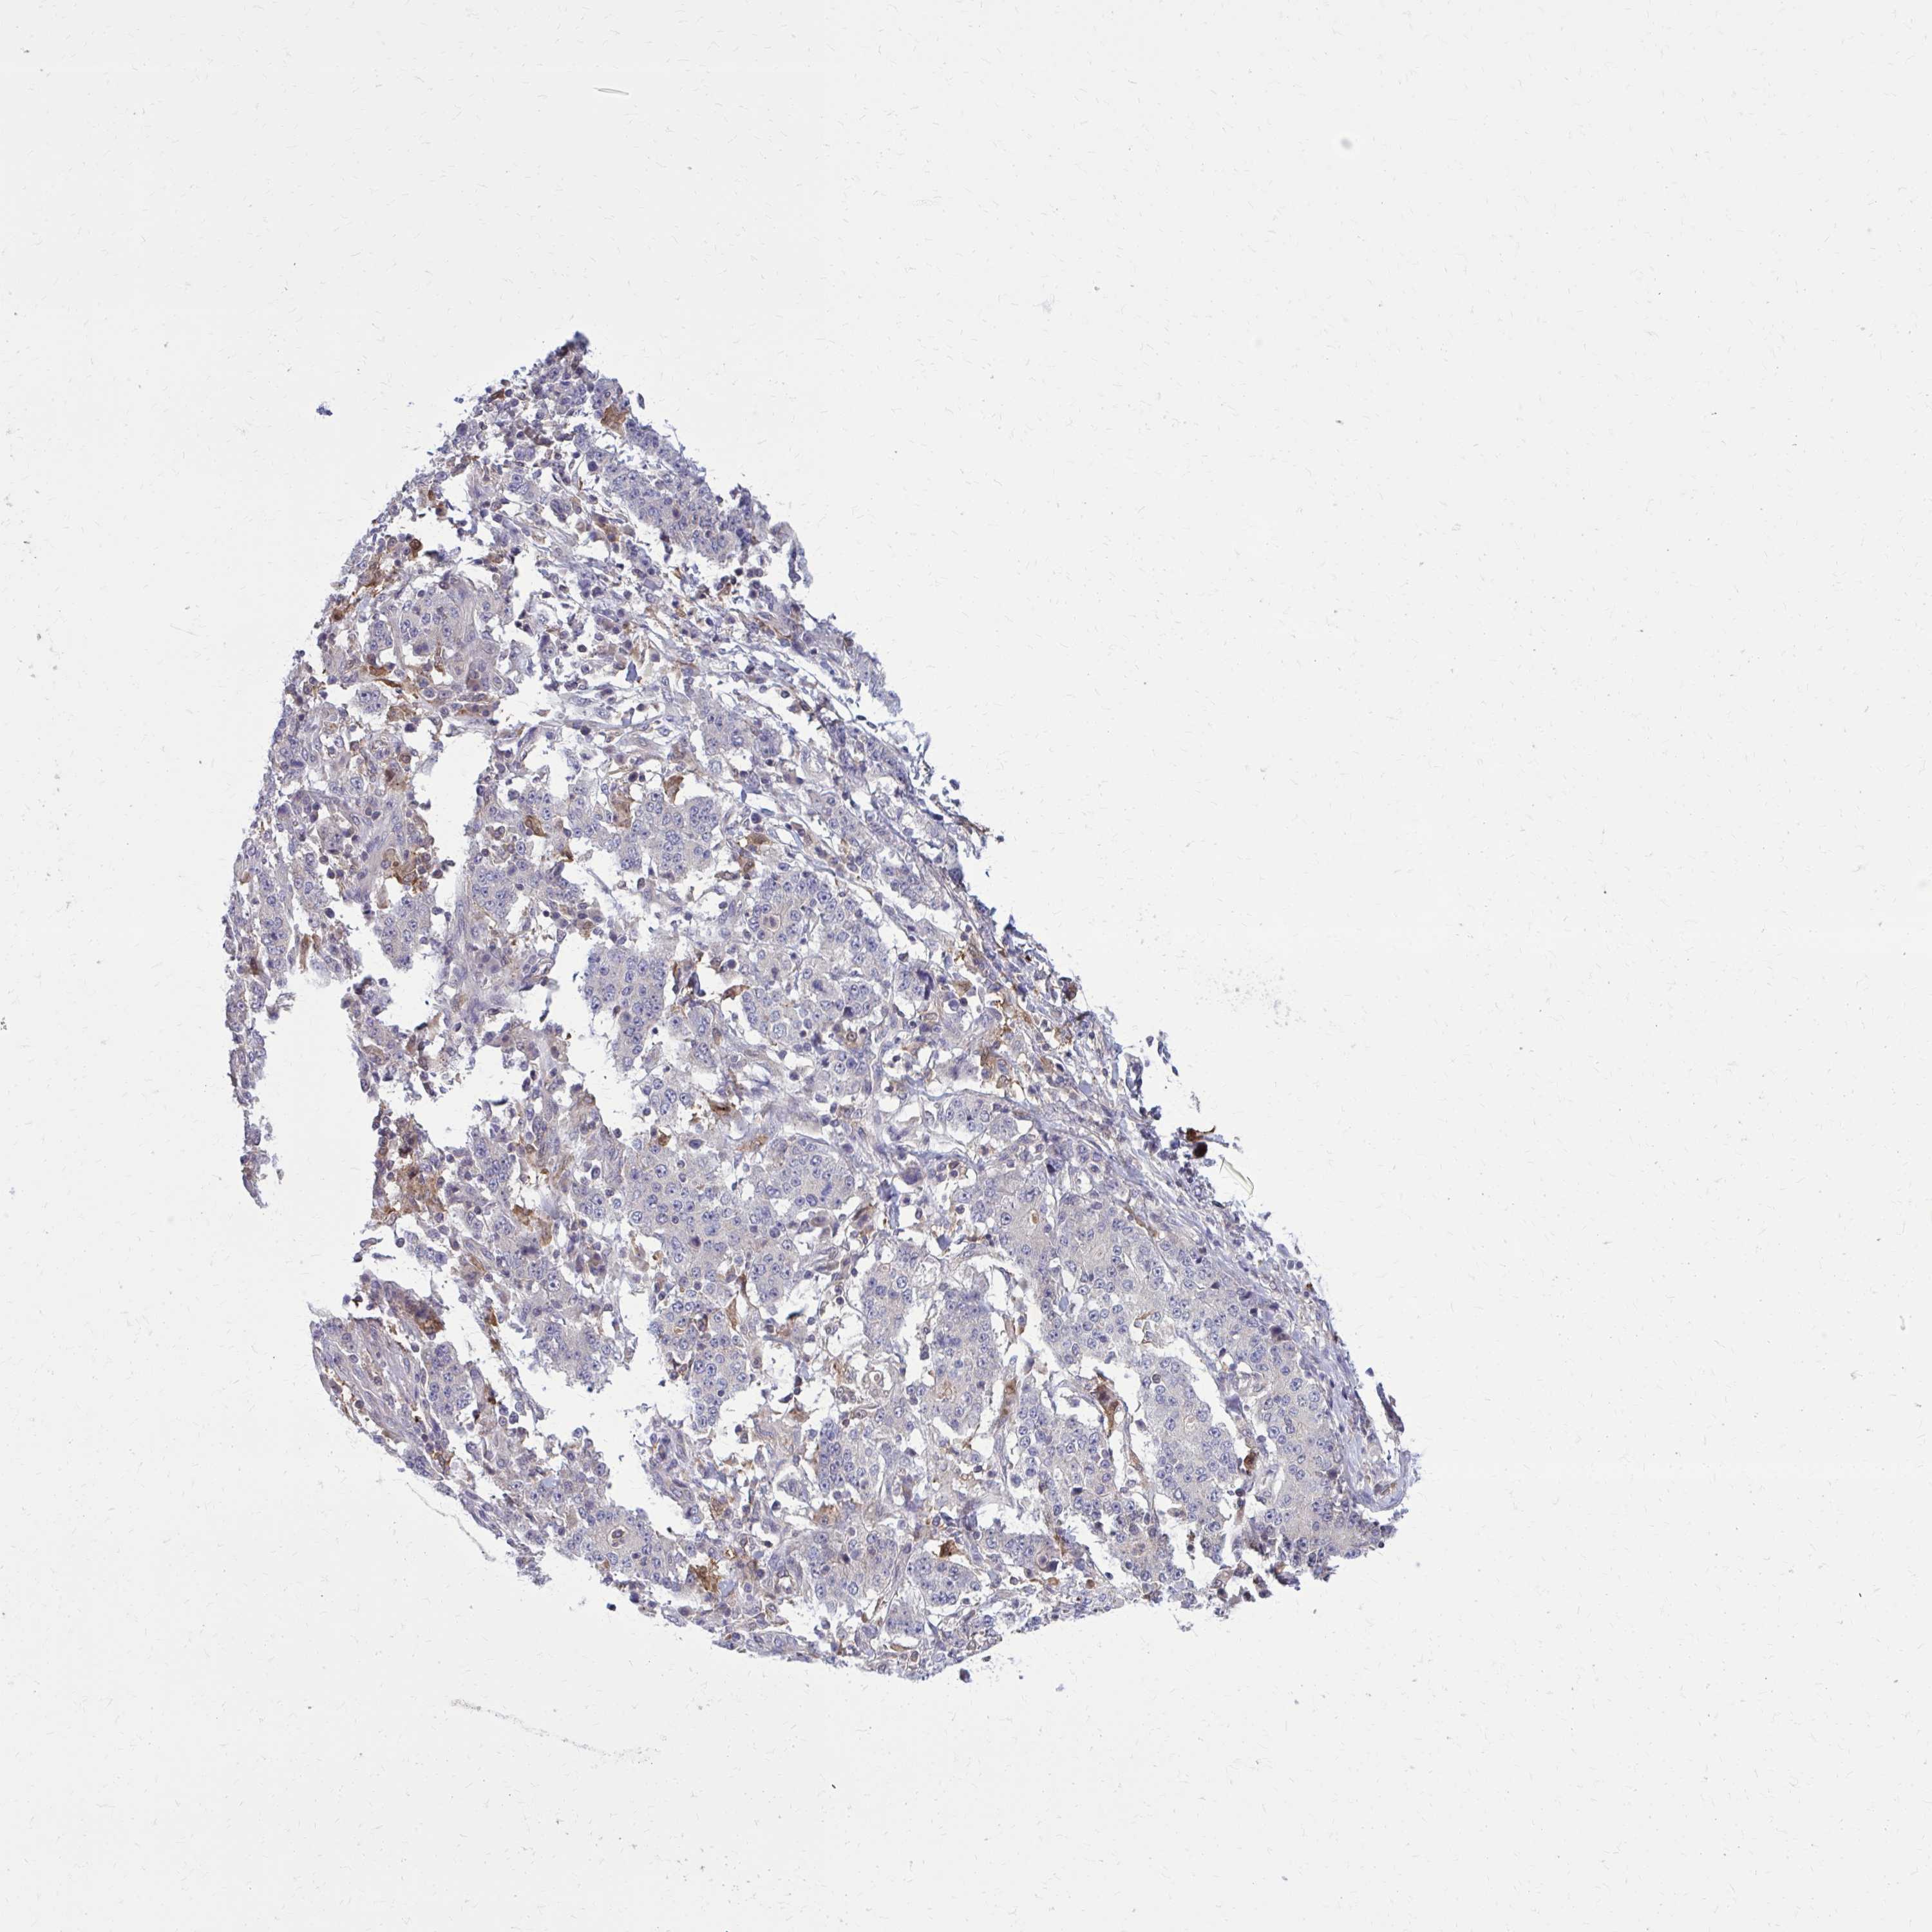

STOMACH CANCER - Protein expressioni

A mouse-over function shows sample information and annotation data. Click on an image to view it in a full screen mode. Samples can be filtered based on level of antibody staining by selecting one or several of the following categories: high, medium, low and not detected. The assay and annotation is described here.

Note that samples used for immunohistochemistry by the Human Protein Atlas do not correspond to samples in the TCGA dataset.

Antibody stainingi

Antibody staining in the annotated cell types in the current human tissue is reported as not detected, low, medium, or high, based on conventional immunohistochemistry profiling in selected tissues. This score is based on the combination of the staining intensity and fraction of stained cells.

Each image is clickable and will lead to virtual microscopy that enables deeper exploration of all samples and also displays staining intensity scores, fraction scores and subcellular localization as well as patient and tissue information for each sample.

Antibody HPA051428

Staining

High

Medium

Low

Not detected

Intensity

Strong

Moderate

Weak

Negative

Quantity

>75%

75%-25%

<25%

None

Location

Nuclear

Cytoplasmic/membranous

Cytoplasmic/membranous,nuclear

Adenocarcinoma, NOS